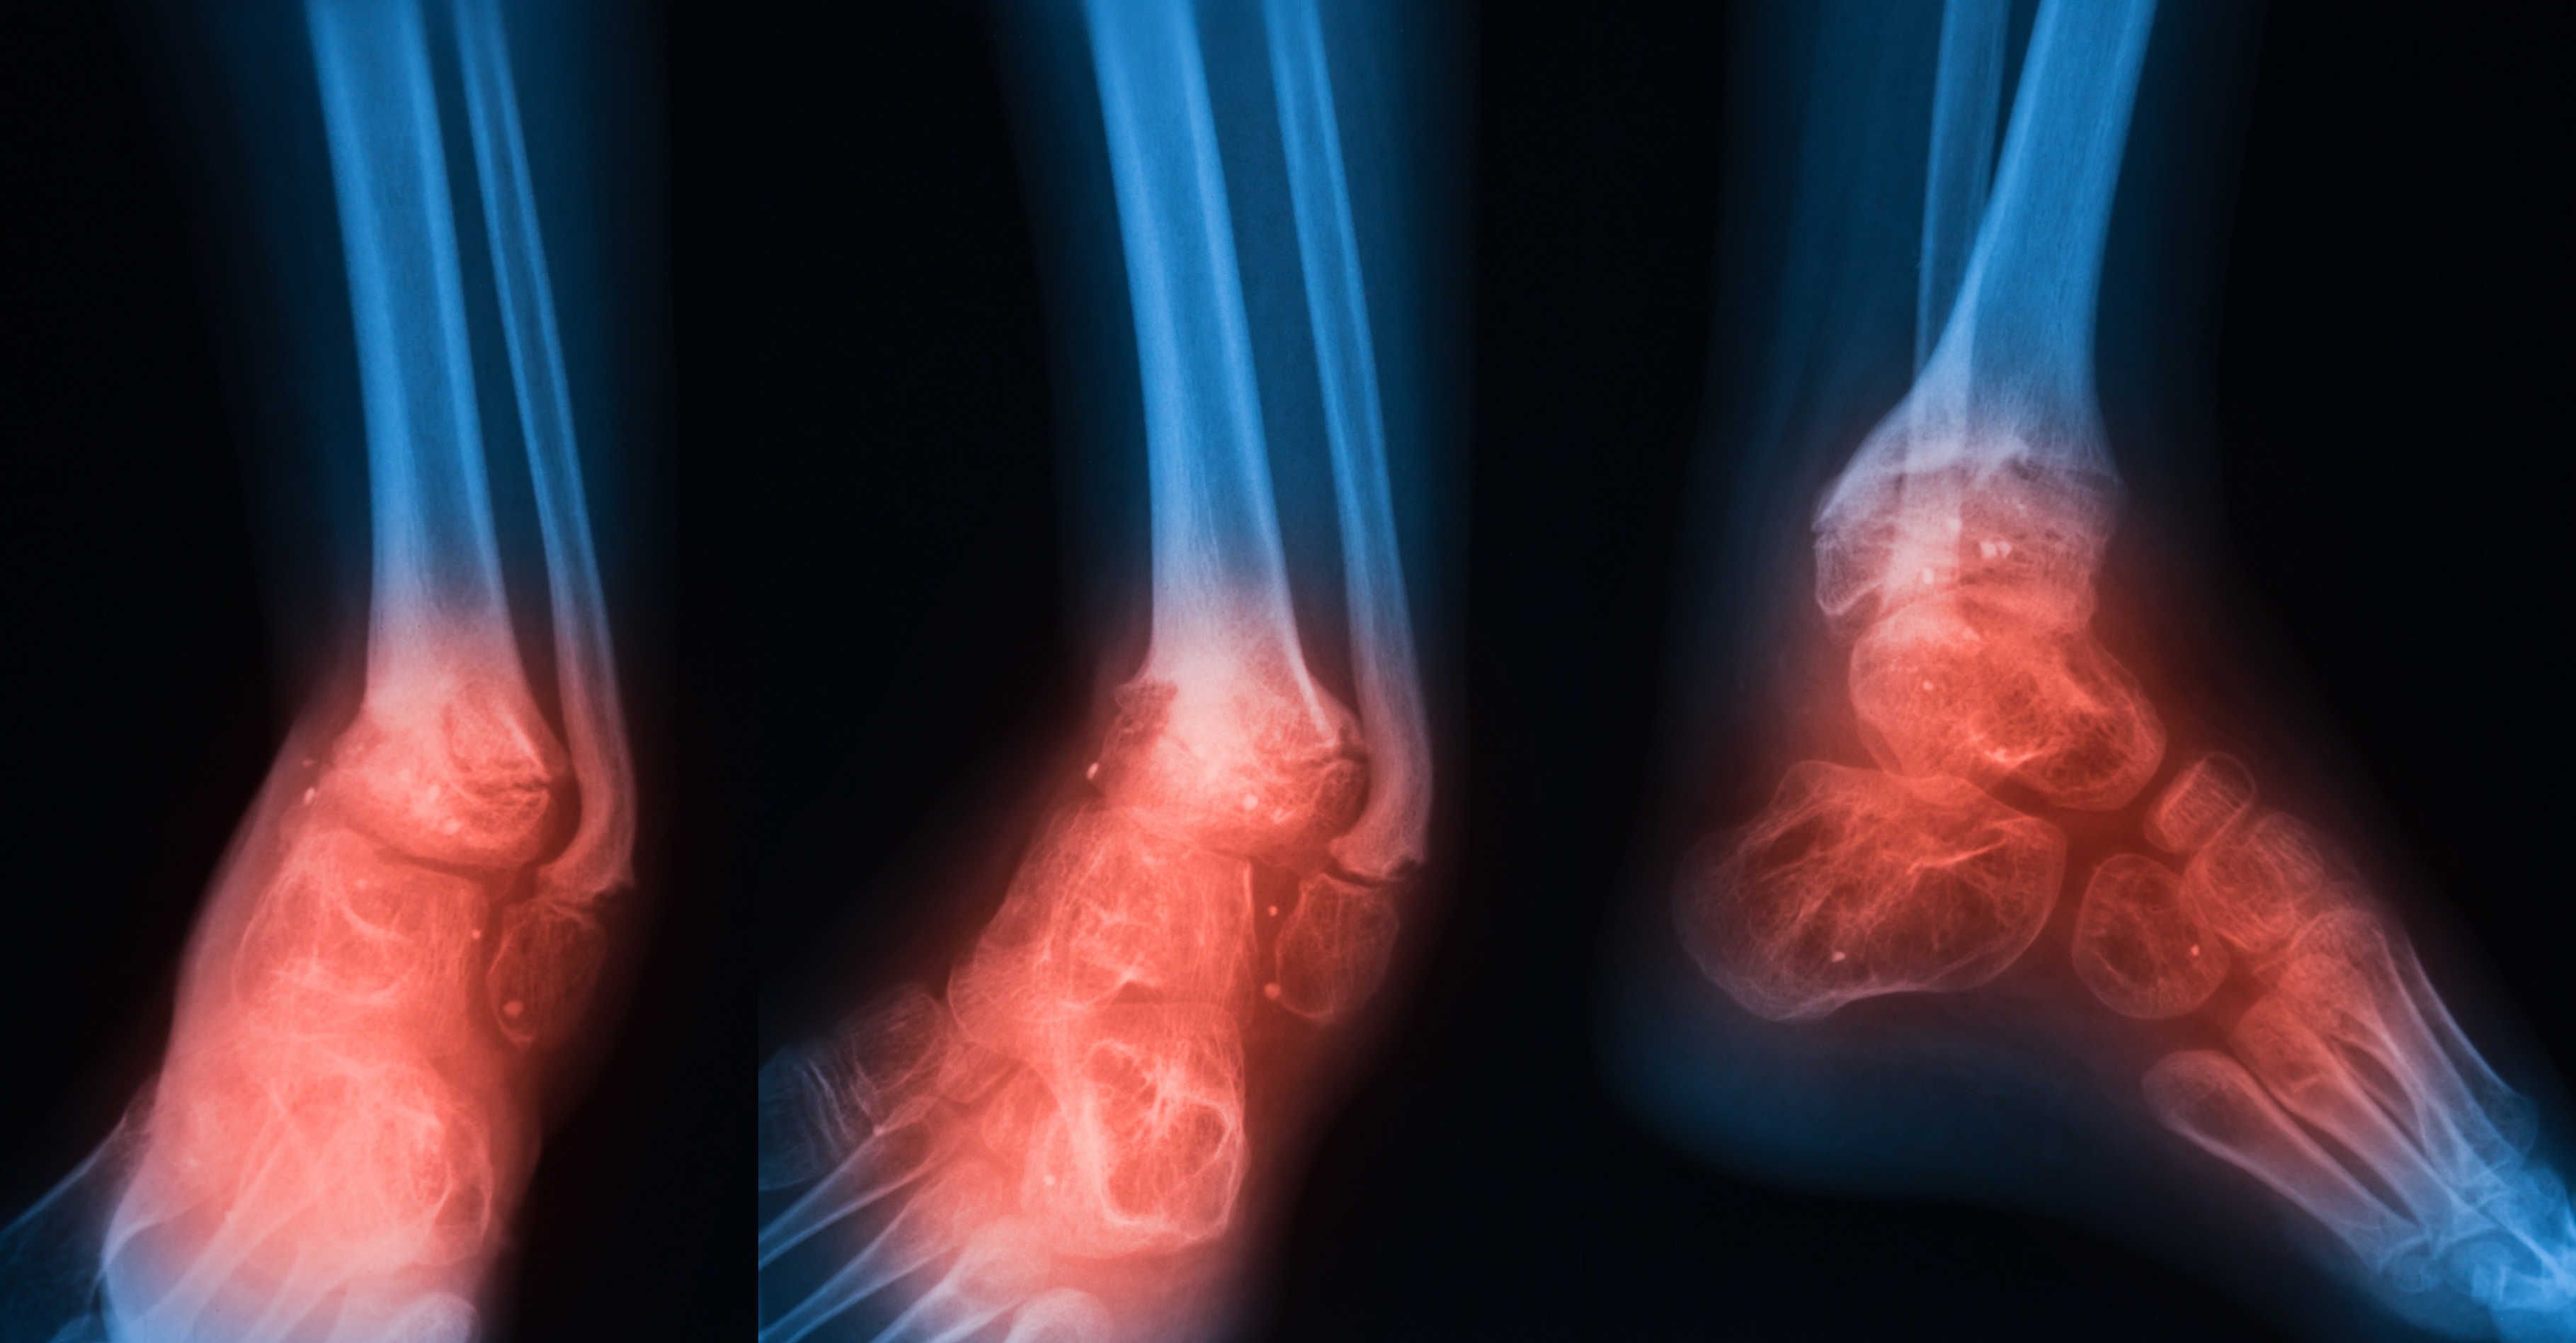

Pernahkah terjadi situasi di mana anda sedang membongkok, mencangkung atau sekadar bergerak kecil dan tiba-tiba sahaja keluar bunyi pada lutut? Sekiranya ia berlaku dan berulang, adakah anda tahu apa punca lutut berbunyi? Teruskan baca artikel ini dengan lebih lanjut! Untuk mendapatkan lebih banyak informasi berkenaan Tulang & Otot, anda boleh klik di sini. Apa maksud, simptom & […]